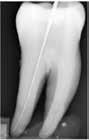

Fig. 3. 2D røntgenoptagelser, som viser fire tænder henholdsvis før guttaperkafjernelse (A1, B1, C1 og D1) samt efter (A2, B2, C2 og D2). Ved A og B er der anvendt termisk teknik samt efterfølgende ParaPost bor. Der ses generelt en guttaperkafjernelse, der følger rodkanalen. Ved C og D er der gjort brug af den mekaniske teknik samt efterfølgende ParaPost bor. Ved sammenligning fra C1 til C2 ses, at proceduren har ført til en reduktion af risikolinjen (pil). Ved sammenligning fra D1 til D2 ses det, at præparationsdybden er blevet mere end dobbelt kronehøjde.

Fig. 3. 2D radiographs illustrate four teeth before gutta-percha removal (A1, B1, C1 and D1) and after (A2, B2, C2 and D2). At A and B the gutta-percha was removed with the thermal technique and followed by ParaPost drill. In general, the removal follows the gutta- percha. At C and D the gutta percha was removed with the mechanical technique and followed by the ParaPost drill. When comparing C1 to C2 the procedure has led to a reduction of the risk line (arrow). When comparing D1 to D2 the preparation depth has become more than twice the height of the crown.